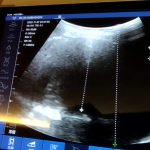

掌超家用:居家动态监测胸水第一例-(20221129)   (一)背景 患者肖绍博(居家管护代号BXS0406),男,78岁,2022年4月在北京某三甲医院经病理会诊确诊为“恶性胸膜间皮瘤”后,出院居家谋求/实施中西医结合综合康养最适方案,请北京慧家健康信息力研究院(BHI)助力。 该患者可定量检测/监测的主要临床异常是胸部CT或B超显示“左侧大量胸水”,相...

20220927,周二,晴 #抗癌健康日记# 与#健康管护记录# 确诊罕见凶险的癌症已半年,坚持看中医吃中药5个月,今天是第6次中医专家面诊,汇报了连续5个月胸水情况,胸水从最高16cm,先降到10cm,后又缓慢增长,一周前测得15cm。 中医专家号了脉,看了舌苔。嘱:一定不能着凉。饮食不要西方化(不要肉鱼虾等高蛋白,不要水果)。调整中药方子,去一味药,增加...